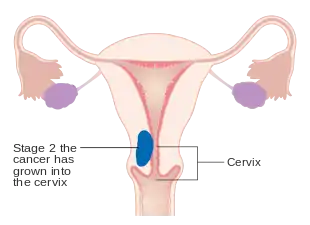

Staging

Endometrial carcinoma is surgically staged using the FIGO cancer staging system. The 2009 FIGO staging system is as follows:[63][64]

| Stage | Description |

|---|---|

| IA | Tumor is confined to the uterus with less than half myometrial invasion |

| IB | Tumor is confined to the uterus with more than half myometrial invasion |

| II | Tumor involves the uterus and the cervical stroma |

| IIIA | Tumor invades serosa or adnexa |

| IIIB | Vaginal and/or parametrial involvement |

| IIIC1 | Pelvic lymph node involvement |

| IIIC2 | Para-aortic lymph node involvement, with or without pelvic node involvement |

| IVA | Tumor invades bladder mucosa and/or bowel mucosa |

| IVB | Distant metastases including abdominal metastases and/or inguinal lymph nodes |

Myometrial invasion and involvement of the pelvic and para-aortic lymph nodes are the most commonly seen patterns of spread.[2] A Stage 0 is sometimes included, in this case it is referred to as "carcinoma in situ".[9] In 26% of presumably early-stage cancers, intraoperative staging revealed pelvic and distant metastases, making comprehensive surgical staging necessary.[27]

Stage IA and IB endometrial cancer

Stage IA and IB endometrial cancer Stage II endometrial cancer

Stage II endometrial cancer Stage III endometrial cancer

Stage III endometrial cancer Stage IV endometrial cancer

Stage IV endometrial cancer